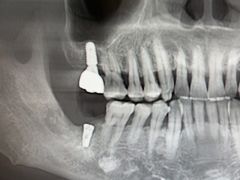

• 牙博士口腔品牌连锁(杨浦店)

• -牙博士口腔品牌连锁(杨浦店)

070103的 | 23-02-12